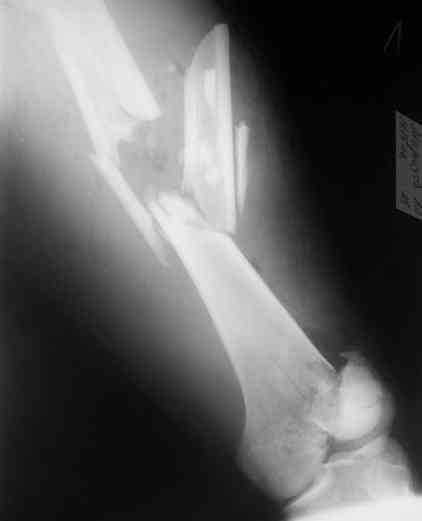

А в чем проблемы? Пример в приложении.

В приложении функциональные снимки в 3 мес. и в 1 год.